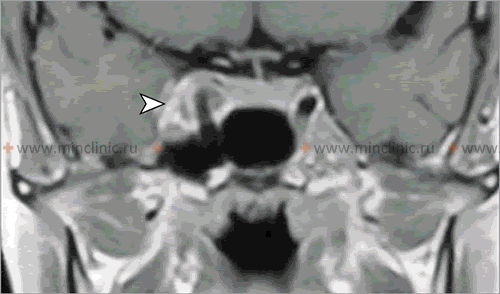

Neuroimaging techniques like Magnetic Resonance Imaging (MRI) play a crucial role in evaluating suspected orbital and potential intracranial complications arising from inflammation of the nasal cavity and paranasal sinuses.

- MRI of the Orbits and Brain with Gadolinium Contrast: MRI provides superior soft tissue contrast and is often complementary or preferred if CT is equivocal, if intracranial complications are strongly suspected, or for evaluating specific structures like the optic nerve or cavernous sinus [9]. Advantages include:

- Better differentiation between phlegmon (diffuse inflammation/cellulitis) and drainable abscess.

- Superior visualization of optic nerve inflammation (optic neuritis).

- High sensitivity for detecting early intracranial complications like meningitis (leptomeningeal enhancement), epidural/subdural empyema, brain abscess.

- Excellent evaluation of cavernous sinus pathology (thrombosis, inflammation) - often combined with MR Venography (MRV).

- Diffusion-weighted imaging (DWI) sequence is highly sensitive for detecting restricted diffusion within abscess collections (pus), confirming their purulent nature.